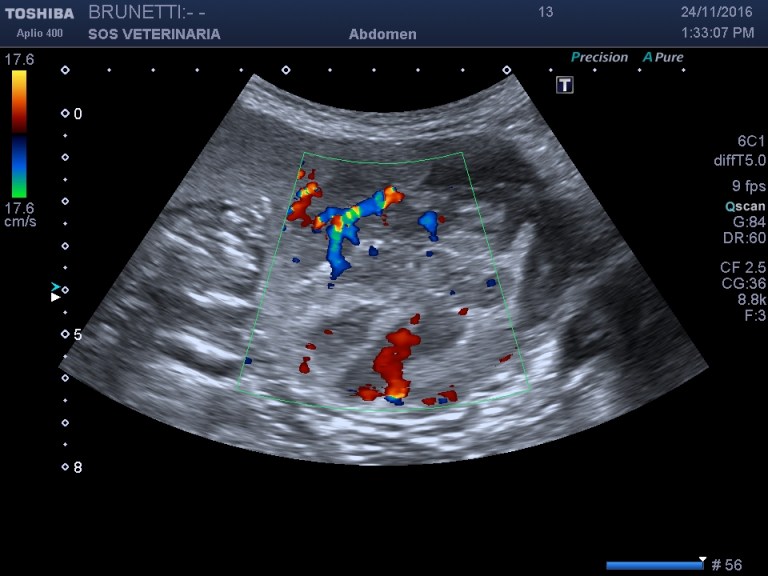

Esame ecografico

massa (circa 6 cm) situata caudalmente verso la coda dell organo eterogena nelle porzioni centrali ,omogena e simile al parenchima sano alla periferia , ben demarcata ,interrompe bruscamente il profilo dell organo,segnali colore doppler moderati non distribuiti omogeneamente e uniformemente